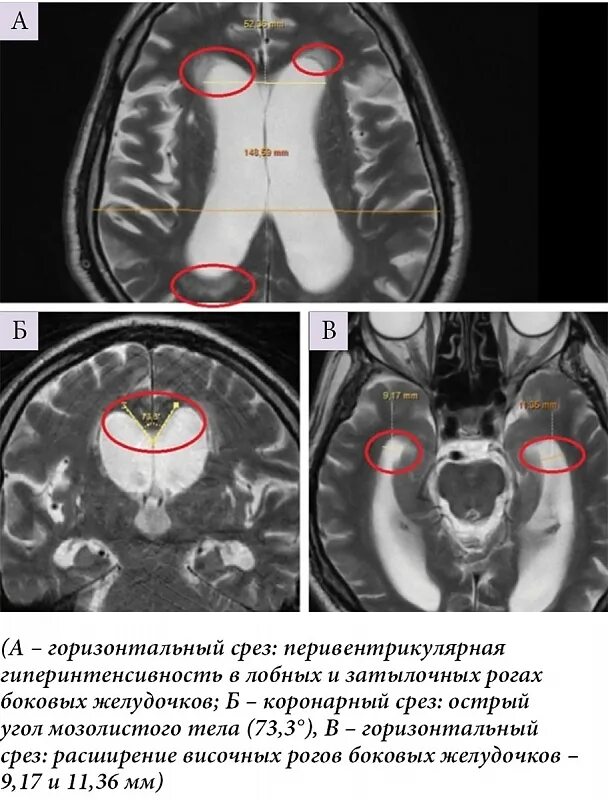

Расширение ликворосодержащих пространств